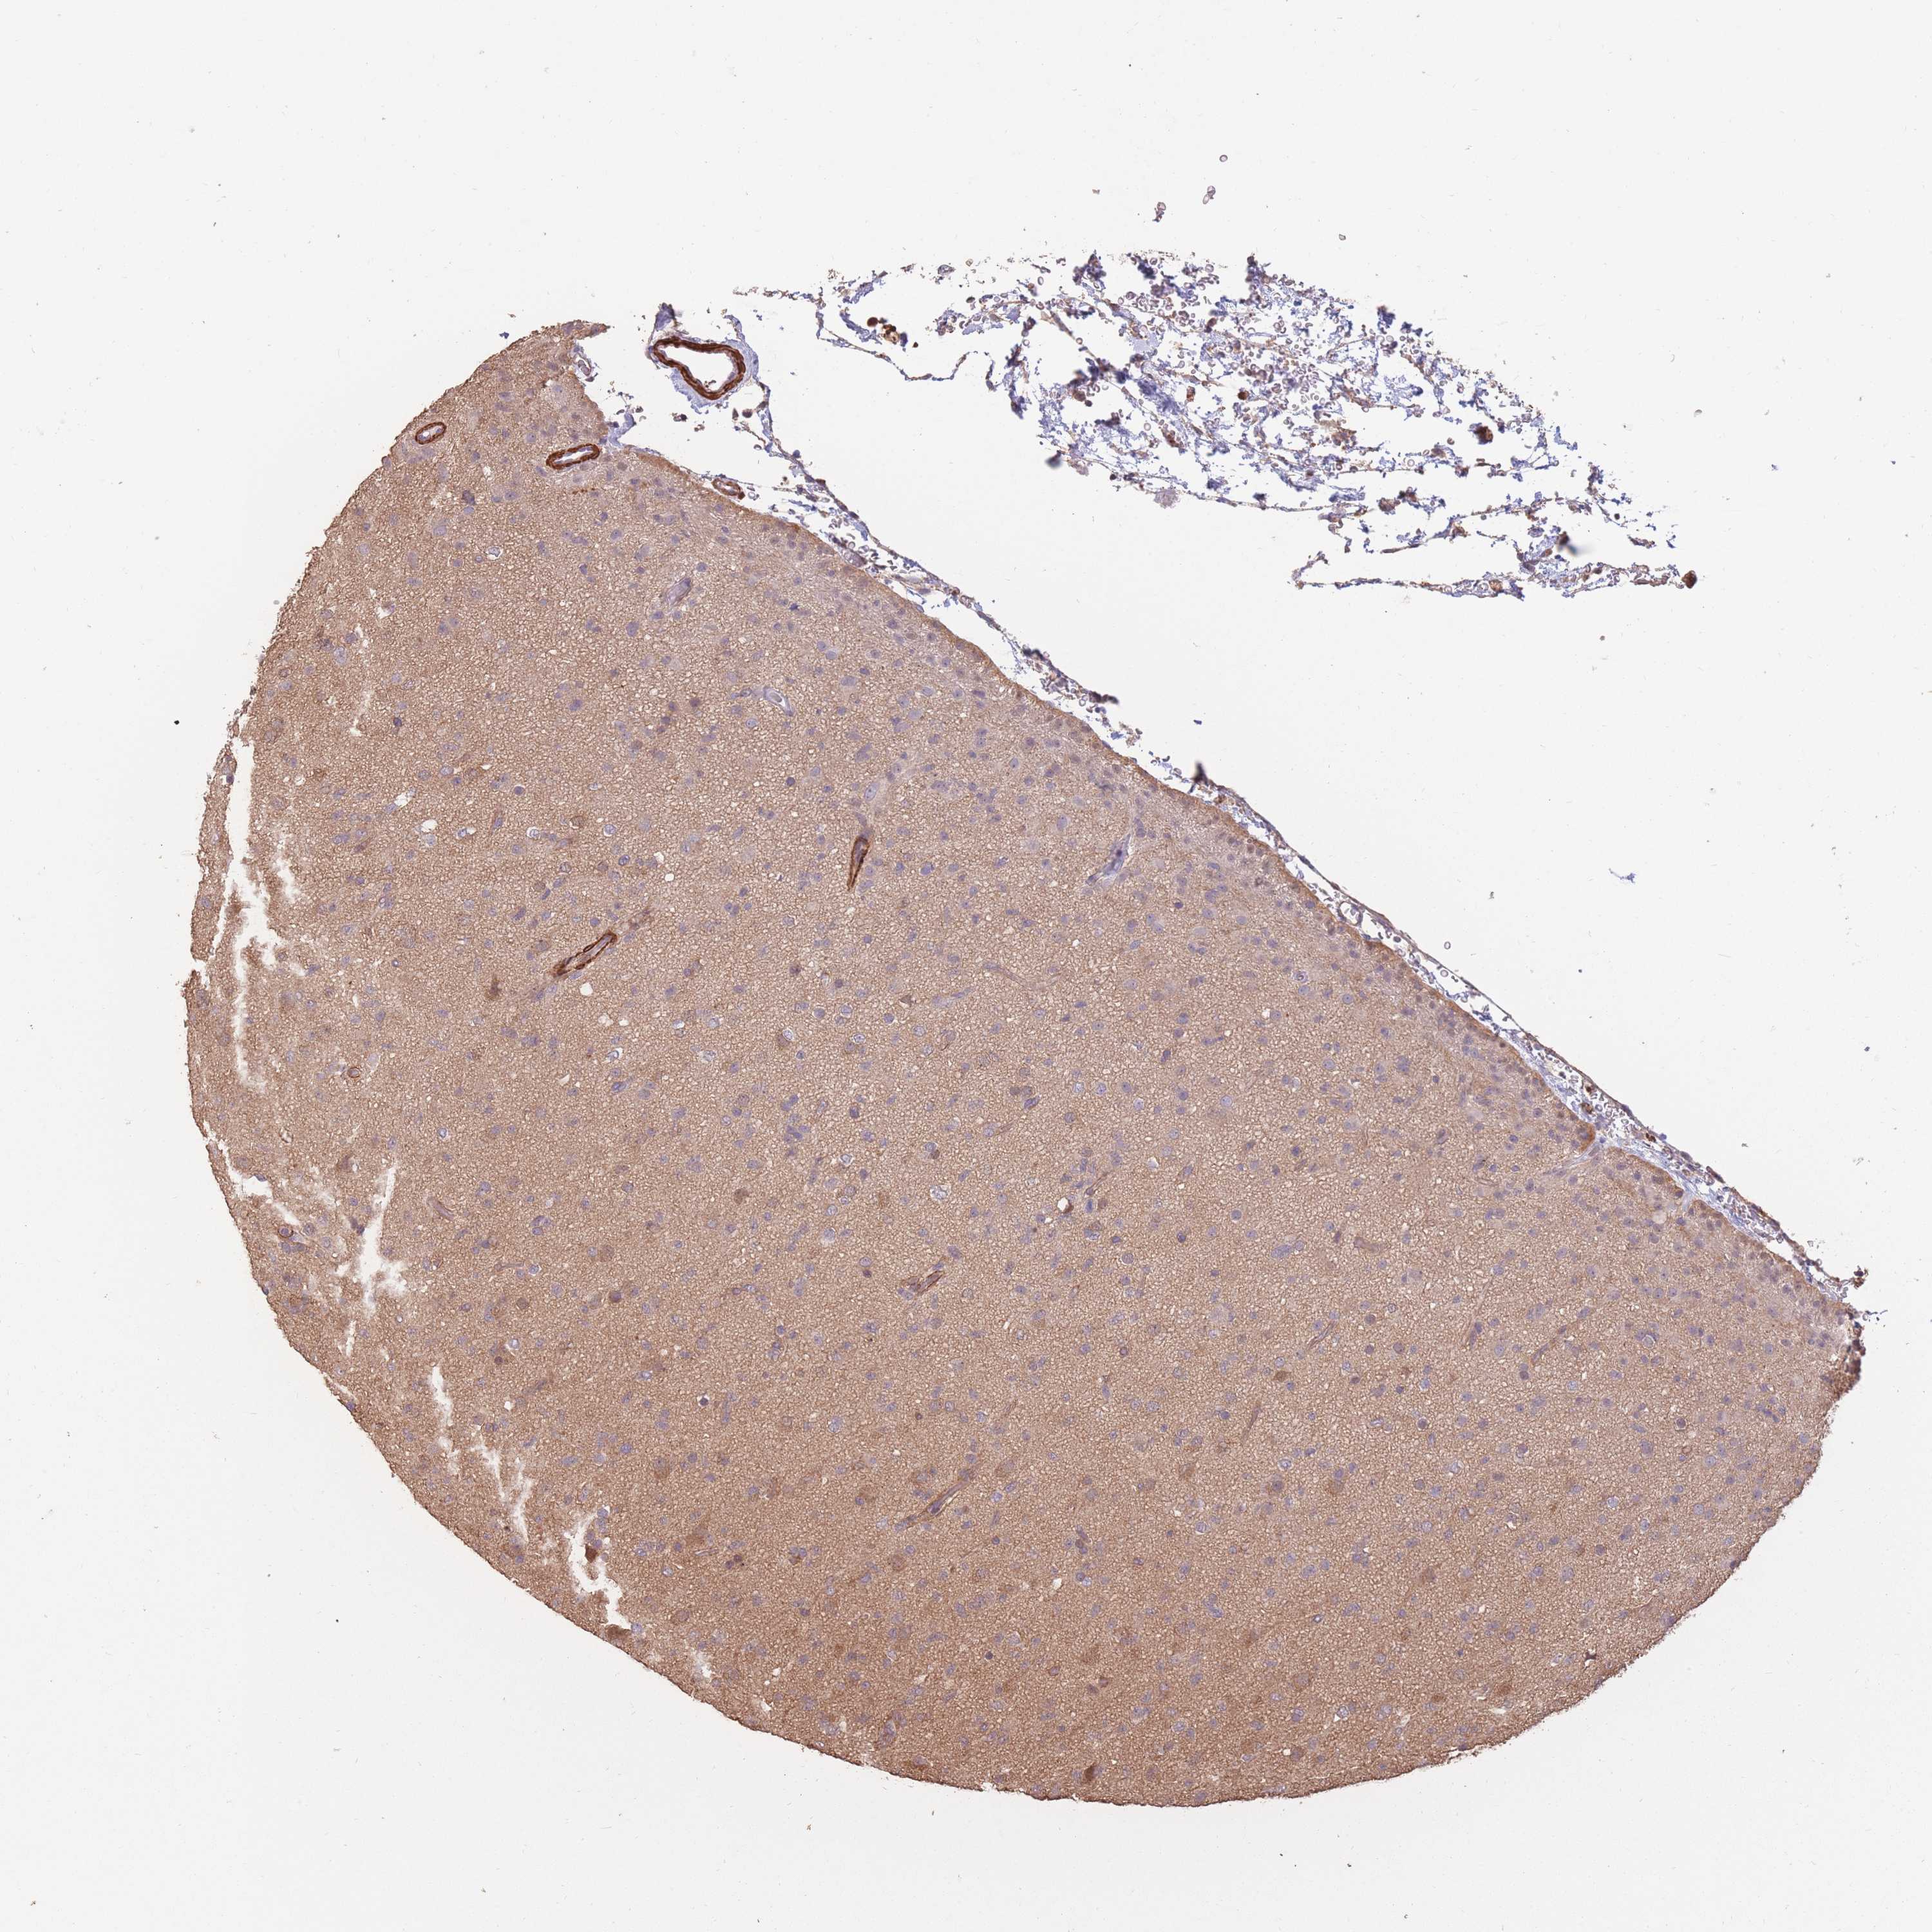

GLIOMA - Protein expressioni

A mouse-over function shows sample information and annotation data. Click on an image to view it in a full screen mode. Samples can be filtered based on level of antibody staining by selecting one or several of the following categories: high, medium, low and not detected. The assay and annotation is described here.

Note that samples used for immunohistochemistry by the Human Protein Atlas do not correspond to samples in the TCGA dataset.

Antibody stainingi

Antibody staining in the annotated cell types in the current human tissue is reported as not detected, low, medium, or high, based on conventional immunohistochemistry profiling in selected tissues. This score is based on the combination of the staining intensity and fraction of stained cells.

Each image is clickable and will lead to virtual microscopy that enables deeper exploration of all samples and also displays staining intensity scores, fraction scores and subcellular localization as well as patient and tissue information for each sample.

Antibody HPA006592

Staining

High

Medium

Low

Not detected

Intensity

Strong

Moderate

Weak

Negative

Quantity

>75%

75%-25%

<25%

None

Location

Nuclear

Cytoplasmic/membranous

Cytoplasmic/membranous,nuclear

Glioma, malignant, Low grade

Glioma, malignant, High grade